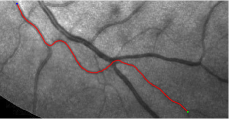

Validation. We validate our minimal path model on respective 54 and 30 patches obtained from the DRIVE [14, 15] and the IOSTAR [16] datasets with AV groundtruth. Each artery involved in these parches locates near a vein or crossing it at least once. Our goal is to extract the artery between two given points. In order to get the quantitative evaluation, we first convert each continuous spatial path to an 4-connected digital path which is considered as a pixel collection. We denote by the collection of digital path pixels inside the artery groundtruth map . Thus, a measure can be simply defined as , where and mean the respective number of elements involved in and . We compare our model to four existing minimal path models: the isotropic Riemannian (IR) model [1], the anisotropic radius-lifted Riemannian (ArR) model [4], the isotropic orientation-lifted Riemannian (IoR) model [5] and the curvature-penalized (CuP) model [7]. The construction of these metrics are based on the OOF outputs [12]. Note that a centerline-based potential is chosen so that we remove the radius dimension of [5] to reduce computation complexity. The results in terms of the score are presented in Table 1, including the average (Avg.), maximum (Max.), minimum (Min.) and standard deviation (Std.) values. In both DRIVE and IOSTAR datasets, our method can achieve the best performances thanks to the coherence penalization. Note that in Table 1, we evaluate our method by using the refined paths instead of using the original coherence-penalized minimal paths. For comparisons in visualization, we show the minimal paths from the ArR metric , the CuP metric and the proposed coherence-penalized metric on three retinal patches as shown in Fig. 3. The targeted artery vessels which cross veins at least once are labeled by red color in column 1. The paths shown in column 4 from the proposed metric are results after refinement. One can claim that our method indeed can catch expected arteries while other metrics fall into the traps of short branches combination.